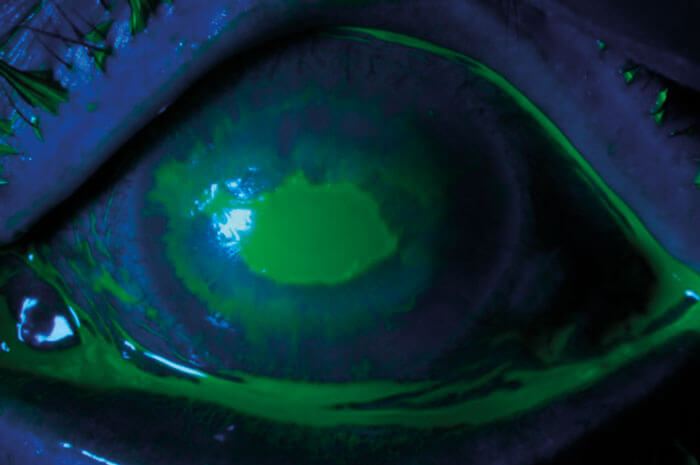

A 67-year-old retired female nurse presented with persistent, bilateral, non-healing (>6 weeks) corneal ulcers and stromal ring infiltrates (Figures 1 and 2). The epithelial defects were the result of chemical burns caused by her contact lenses which had been stored in enzymatic cleaning solution.

Cornea samples were negative for herpes simplex, bacteria and fungi. A tarsorrhaphy was carried out in her left eye (Figure 3). Marked improvement was observed after one week (Figure 4). Prior to performing a tarsorrhaphy in her right eye, we noticed that the patient had been using anaesthetic drops for pain relief (Oxybuprocaine hydrochloride 0.4%). After cessation of the drops and a tarsorrhaphy, the right eye healed as well.